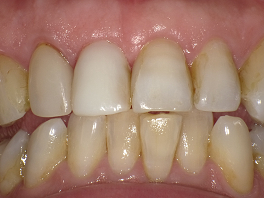

二人目の患者さんも30台の女性の方です。左の一番前の歯が黒いことを気にして来院されました。

この方は、ホワイトコートを希望されて来院されましたが、上の方のグラディアダイレクトの写真とこの後に紹介しているホワイトコートの写真を較べて、グラディアダイレクトをすることになりました。

今回は、歯並びは問題ないのですが、このことで逆に難しくなります。

詰めた分だけ厚みがでて唇に違和感が生じないかどうかです。

しかし、きわめて少ない量で、色を出すことができました。厚みもとても薄くでき、本人にもとても喜んでもらうことができました。

このケースもまったく歯を削っていません。

術前 ↓

術後

隣の歯に合わせて、あまり白くせずに自然な色にしました。

ご本人様からも、とてもすばらしい方法なので、他の方にも教えてあげてほしいということで、快くHPに乗せる承諾をもらいました。